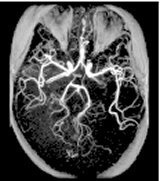

TOF: 3D GRE/SPGR scan

3DTOF uses a volume acquisition to obtain image data and it can be acquired with a GRE or SPGR pulse.

Use 3D TOF-GRE and TOF-SPGR for:

- AVMs

- aneurysms of the Circle of Willis

- intracranial carotid occlusive disease

- 3D TOF generates source, collapsed, and projection images.